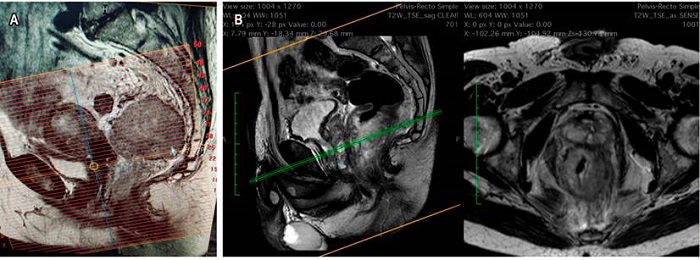

La RM simple con protocolo de recto es el examen principal para el estadiaje y para definir la subclasificación del T, el CRM y la presencia de EMVI. El recto inferior aporta otros parámetros, como la relación del tumor con el mecanismo esfinteriano externo y el surco interesfintérico. Reportar adecuadamente el CRM implica la descripción perfecta de la FMR. Reconocerla en las imágenes es lo que, en últimas, contribuye a establecer un estadiaje adecuado, a tomar las decisiones del manejo oncológico y a planear la técnica quirúrgica.

Si se tomó la decisión de neoadyuvancia por CRM positiva, o por riesgo de estarlo, la reestadificación se hace con una RM simple adicional, con evaluación de las secuencias de T2, de restricción a la difusión y el índice de regresión tumoral. Esta evaluación se hará dependiendo del tipo de neoadyuvancia que se realice: si es convencional, a las 6 semanas de haber terminado la radioterapia, pero si fue TNT (nuevo concepto), la medición se hará al terminar la quimioterapia de consolidación. Una de las dificultades frecuentemente encontradas en el estudio es que habitualmente se solicita como RM de pelvis. Si no se especifica y se solicita la RM con protocolo de recto, el técnico hará la alineación y la reconstrucción de las imágenes en forma inadecuada, y estas no serán perpendiculares al eje del recto y el tumor, lo que no permite evaluar correctamente la subclasificación del T. Es recomendable establecer, con su grupo de trabajo, la revisión de la técnica de reconstrucción de imágenes (Figura 5)14,15.